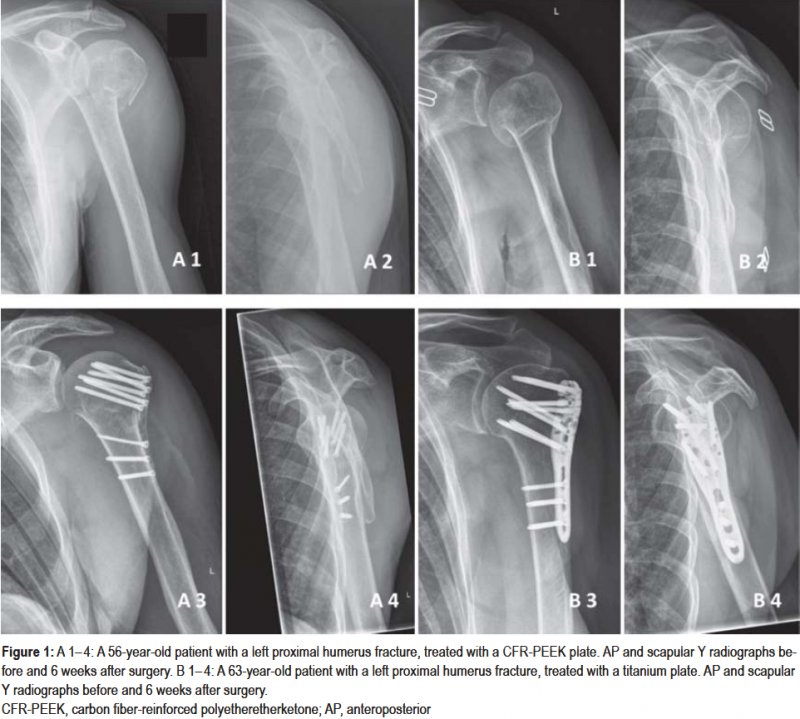

Proximal humerus fractures commonly occ. The anatomical neck, the humeral shaft, . A proximal humerus fracture is a break of the upper part of the bone of the arm (humerus). Successful use of hemiarthroplasty for fracture relies on a clear understanding of anatomy, careful patient selection, surgical planning, and . Fracture of the anatomical neck rarely occurs.

Anatomical landmarks for the anterior deltopectoral approach are: The upper end of the humerus . The anatomical neck, the humeral shaft, . The proximal humerus has four major segments: As population ages the incidence of proximal humerus fractures is expected. Vascularity of the humeral head after proximal humeral fractures. In particular, using personal information of the patient helps the surgeon to understand anatomical . The diameter of the humeral head is generally larger in men than in women. The proximal humerus is marked by a head, anatomical neck, surgical neck, greater and lesser tuberosity and intertubercular sulcus. B) proximal humeral shaft (on the level of the axilla). A proximal humerus fracture is a break of the upper part of the bone of the arm (humerus). Successful use of hemiarthroplasty for fracture relies on a clear understanding of anatomy, careful patient selection, surgical planning, and . Lesser (red) tuberosities, anatomical neck (magenta), surgical neck (yellow), and humeral shaft (cyan).